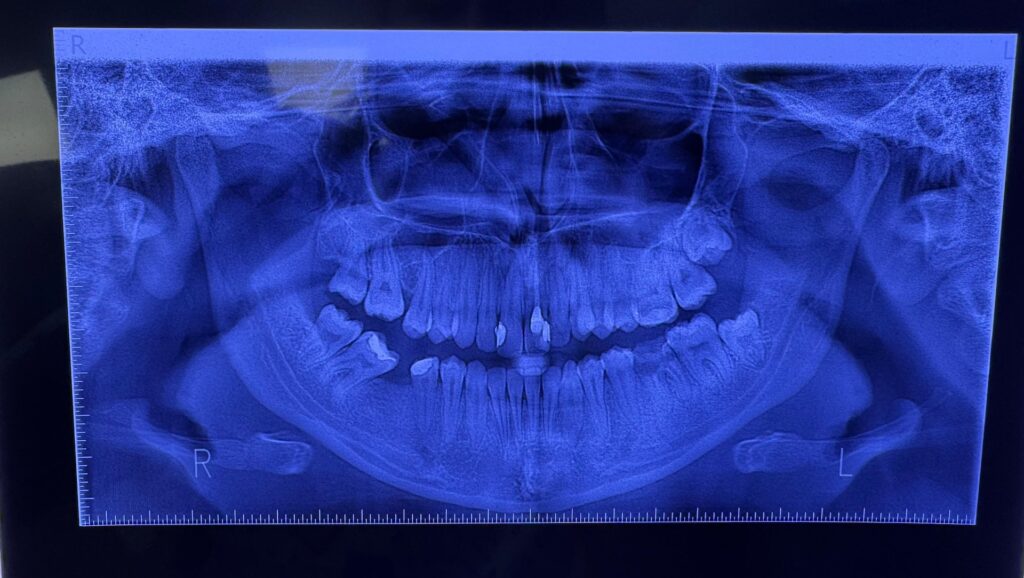

„Nu există o limită de vârstă strictă pentru tratamentul ortodontic. Dinții pot fi repoziționați eficient și la maturitate. Diferența este că, la adulți, oasele maxilare nu mai sunt în creștere, ceea ce poate prelungi ușor durata tratamentului”, precizează dr. Bădoi.

Înghesuirea dentară sau spațiile mari între dinți sunt des întâlnite și îngreunează igiena, favorizând apariția cariilor și a inflamațiilor gingivale.

„Mușcătura incorectă poate duce în timp la uzură neuniformă, fisuri ale smalțului și sensibilitate dentară. Mulți adulți acuză dureri sau zgomote la nivelul articulației temporo-mandibulare, probleme adesea puse pe seama stresului, dar care pot avea cauze ortodontice”, explică medicul.

În timp, dinții greu de curățat pot favoriza și apariția bolii parodontale.

„Sănătatea gingiilor și a osului de susținere este esențială. Dacă există boală parodontală netratată, aceasta trebuie stabilizată înainte de începerea tratamentului ortodontic”, explică dr. Bădoi.

Implanturile nu pot fi deplasate ortodontic, iar coroanele sau punțile necesită o abordare atentă. Pot apărea disconfort sau dificultăți în menținerea igienei, dar cu un plan corect și monitorizare atentă, riscurile pot fi gestionate.